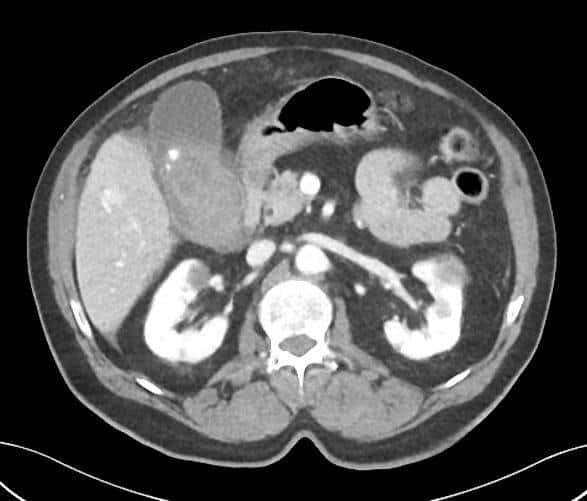

Vỡ túi mật

» Thông tin: Nam giới – 80 tuổi.

» Lâm sàng: Chấn thương.